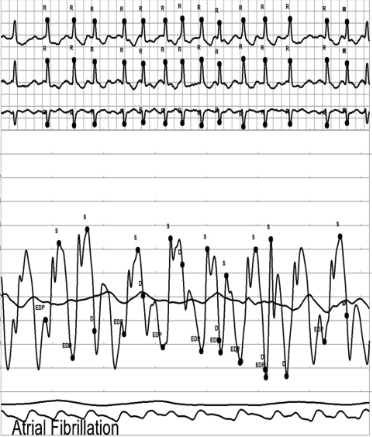

Restrictive cardiomyopathy (RCM) is a rare cardiac condition characterized by stiff and noncompliant ventricular walls, leading to impaired diastolic filling and normal or near-normal systolic function. This condition often presents with subtle symptoms of heart failure. We present a compelling case of longstanding atrial fibrillation (Afib) and atrial flutter (AFL) culminating in refractory cardiogenic shock, ultimately revealing an undiagnosed restrictive cardiomyopathy.

A 40-year-old male with a history of persistent Afib and AFL, unremarkable cardiac MRI on first occurrence for atrial arrhythmias, presented with dyspnea, dizziness, fatigue, and palpitations while on dofetilide. He was found to have atypical AFL with a rapid ventricular response, refractory to pharmacological and electrical cardioversion.

On admission, echocardiography revealed severe right atrial enlargement and grade III diastolic dysfunction. Attempts at rate and rhythm control with multiple agents were unsuccessful. On day 2 of admission, he developed cardiogenic shock (CI 1.5, RA 20, PCWP 40, PA 50/30 [mPA 40], PVR 3, CPO 0.53, PAPI 1.0), necessitating V-A extracorporeal membrane oxygenation and Impella CP for circulatory support.